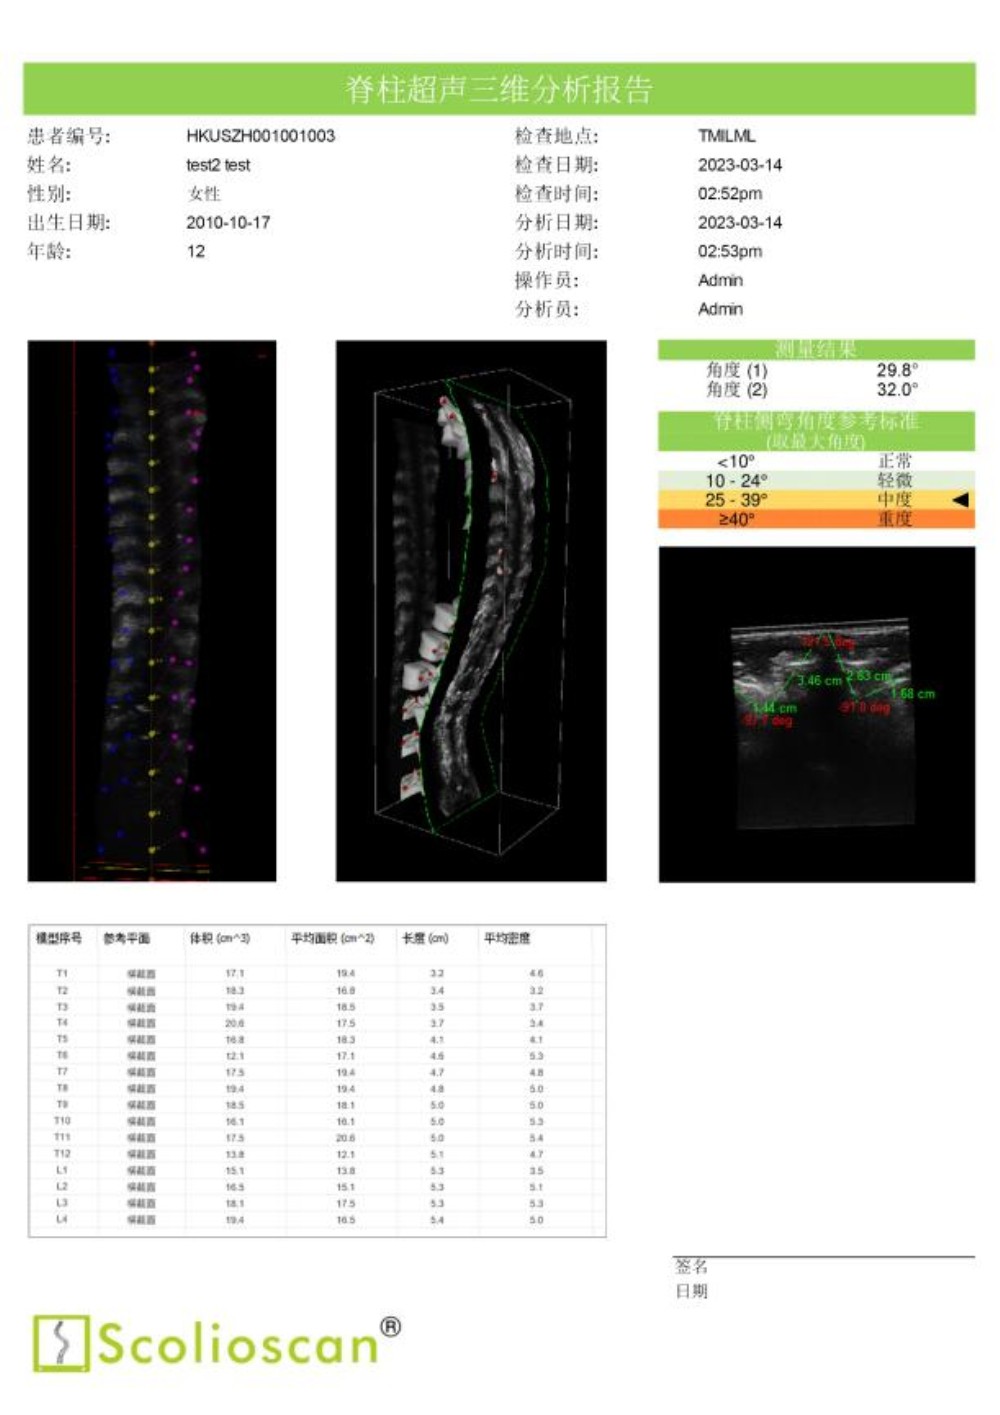

临床试验结果显示,Scolioscan®的测量结果与X光成像高度一致,线性相关度达到0.9464。使用Scolioscan®及早发现青少年的脊柱侧弯问题后,医生得以把握宝贵的黄金治疗时机,通过非手术方式有效控制和治愈疾病,实现早诊断、早治疗、早康复。

通过动态监测侧弯治疗情况,医生能有效帮助孩子选择适合的运动与锻炼方法。密切的超声监测有助于医生在疾病治疗的黄金期积极追踪病情和评估、调整治疗方案,根据脊柱的最新状况,第一时间采用体育运动、手法治疗、支具佩戴等保守疗法为患者矫正,有效减小脊柱侧弯度数。Scolioscan®提供的肌骨三维分析还可以协助医生以关节—肌肉—神经三维度为整体,全面进行脊柱侧弯的综合康复治疗。

内蒙古自治区首台“Scolioscan®无辐射三维超声脊柱侧弯评估系统”成功引入91直播 ,可广泛应用于脊柱侧弯筛查、诊断、病情跟踪和预测以及非手术治疗阶段对治疗结果的可视化反馈和评价等多个领域,为广大儿童青少年提供精准度媲美X光的无辐射、安全的脊柱侧弯评估方案,帮助患有脊柱侧弯的孩子早发现、早干预、早康复,竖起脊梁健康成长。